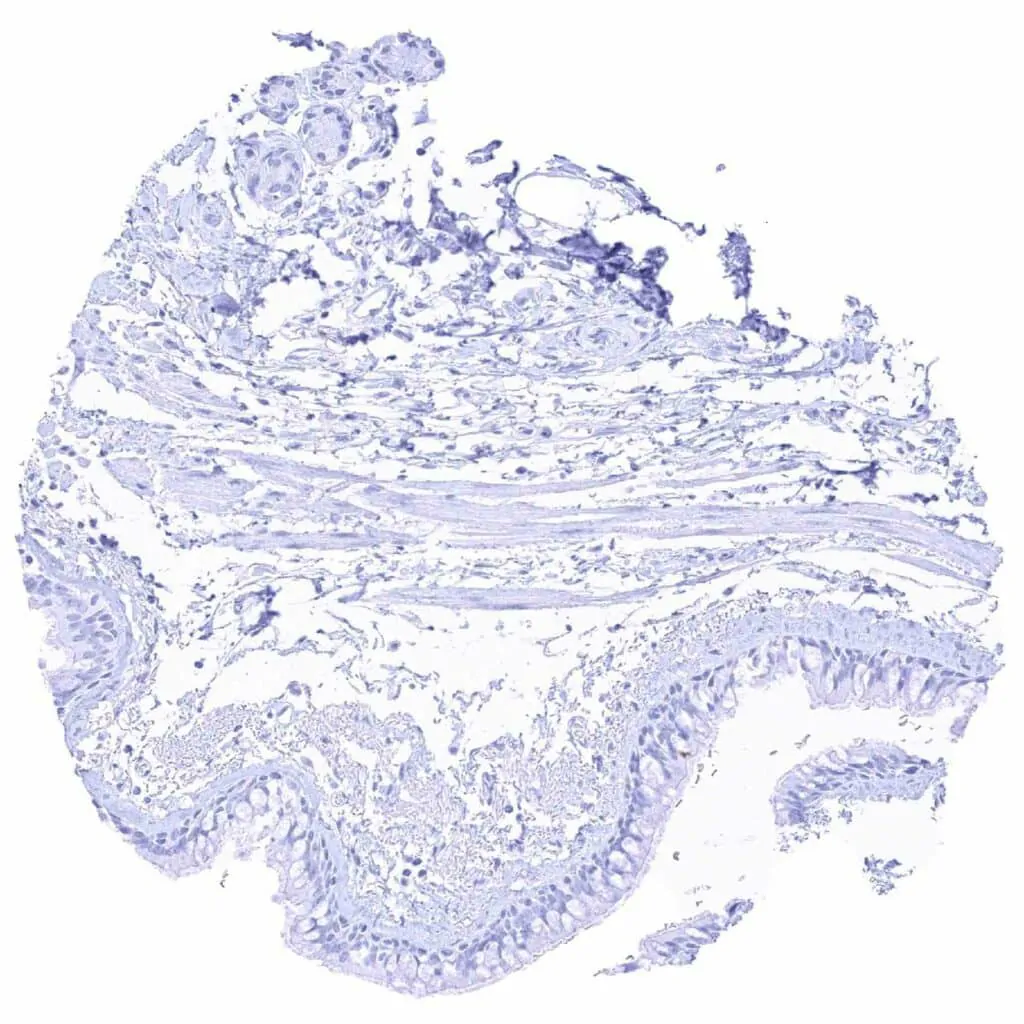

Placenta, mature, amnion and chorion